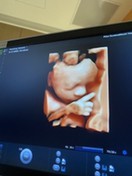

กำลังดูดนิ้วครับ ทีมธันวา☺️☺️